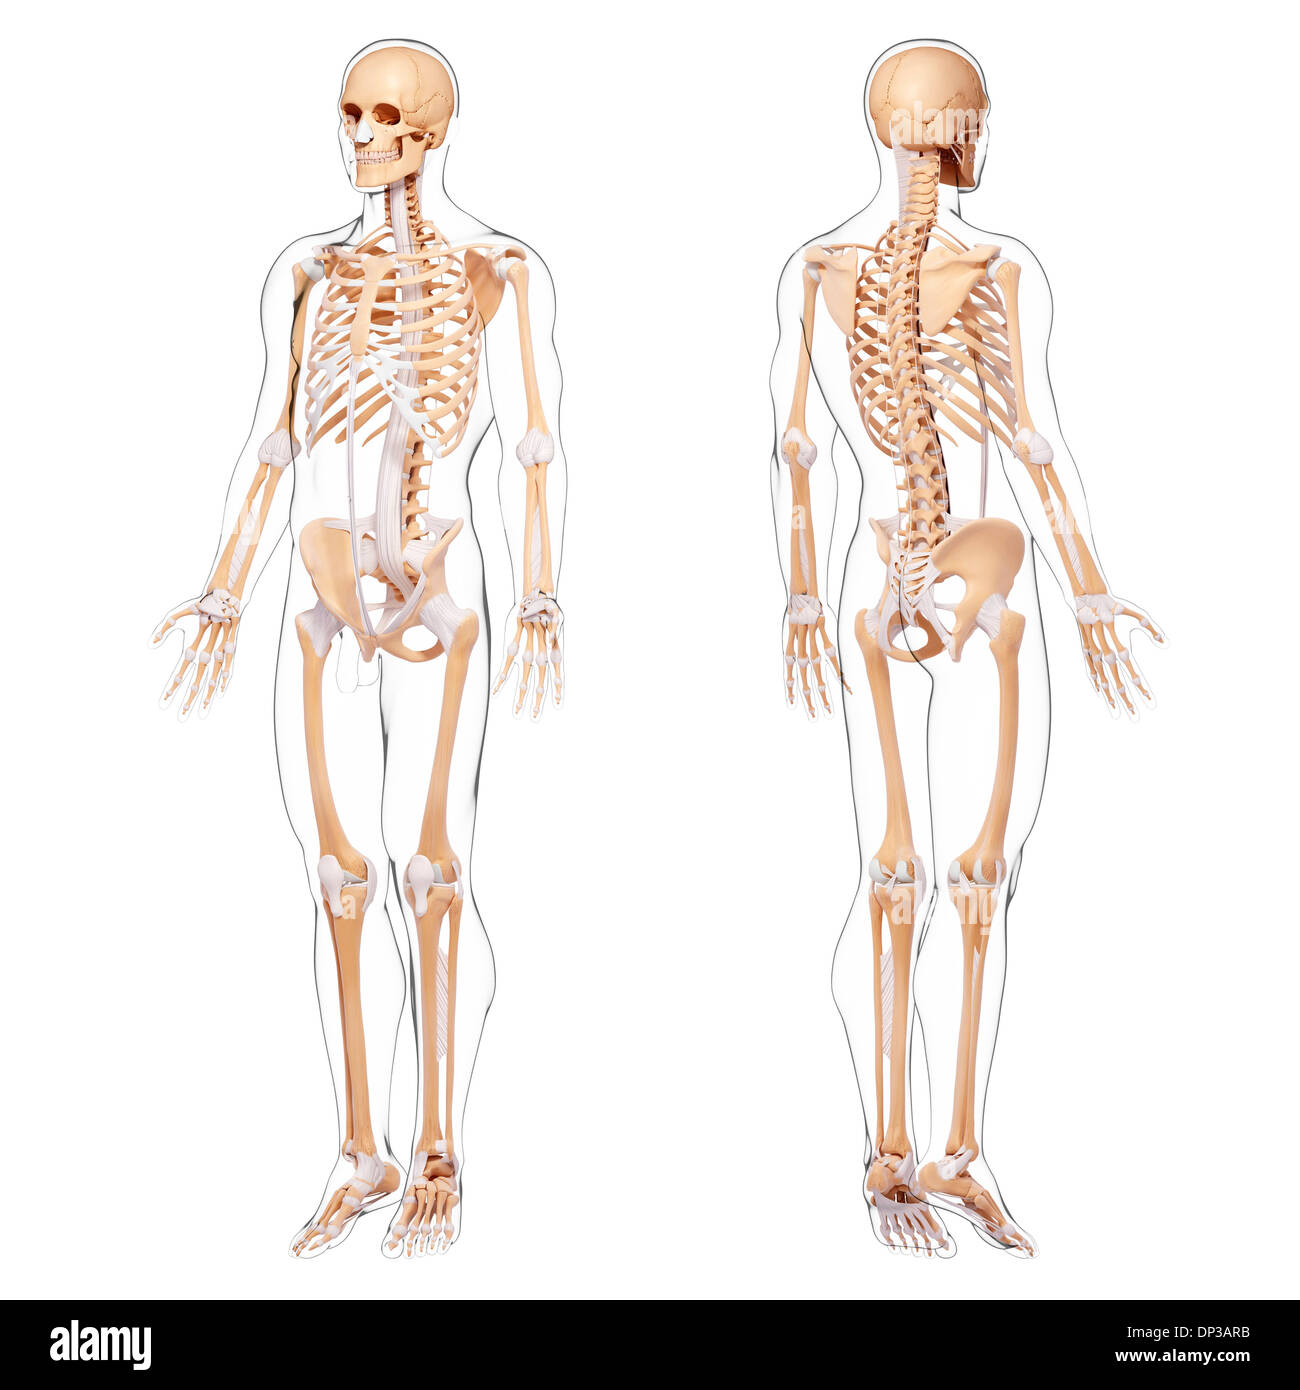

Human Anatomy, artwork Banque D'Imageshttps://www.alamyimages.fr/image-license-details/?v=1https://www.alamyimages.fr/human-anatomy-artwork-image65242387.html

Human Anatomy, artwork Banque D'Imageshttps://www.alamyimages.fr/image-license-details/?v=1https://www.alamyimages.fr/human-anatomy-artwork-image65242387.htmlRFDP4197–Human Anatomy, artwork